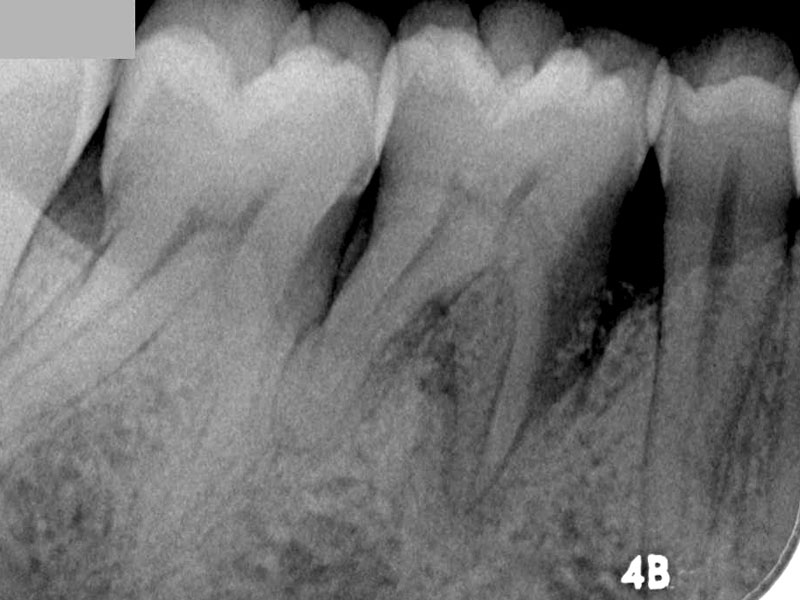

06/08 - Pre-operative radiographRegeneration at LR6 with cerabone® and collprotect® membrane using simple papilla preservation technique - Dr. D. Chatzopoulou